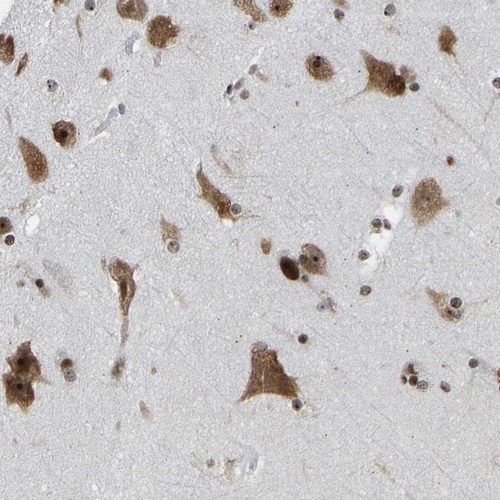

Immunohistochemical staining of human cerebral cortex shows strong cytoplasmic and nuclear positivity in neuronal cells.